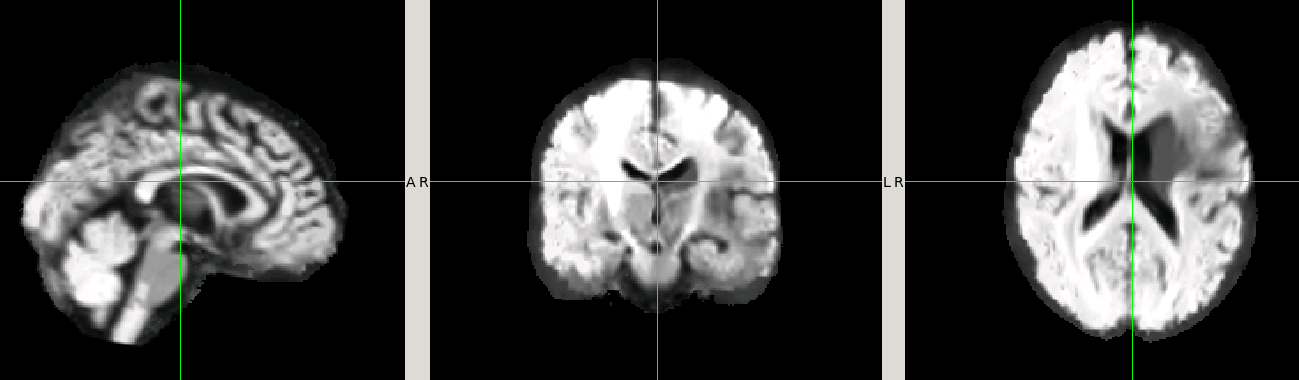

Here is a figure of some registered images along with the IIT HARDI template. The cursor is on the same voxel on all of the images.

A. IIT HARDI template

B. A registered FA map onto the IITmean_FA template using ANTs and the cross-correlation metric for the non-linear registration

C. A registered FOD map onto the IIT HARDI template

D. A registered FA map onto the IITmean_FA template using mrregister

E. A registered FA map onto the IITmean_FA template using ANTs and the Squared Difference metric for the non-linear registration like in mrregister

We tried MRtrix registration using your data. The results are similar to yours. See attached figure. We see shrinking of the brain near the cortex. Based on your tests, it seems that mrregister will shrink the edges of the brain independent on if you are using FODs or FA maps. I wish I had a solution for you. I don't think this is something we can control. I think this is more of an MRtrix issue. I would still be curious to know if you find a solution to this problem.